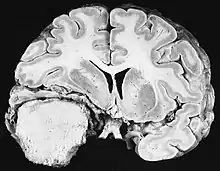

Glioblastome

Les tumeurs des cellules gliales les plus courantes et les plus malignes sont les glioblastomes. Ils consistent en une masse hétérogène de cellules d'astrocytome peu différenciées principalement chez l'adulte. Ils surviennent généralement dans les hémisphères cérébraux, plus rarement dans le tronc cérébral ou la moelle épinière. Sauf dans de très rares cas, comme toutes les tumeurs cérébrales, elles ne s'étendent pas au-delà des structures du système nerveux central.

Le glioblastome peut provenir d'une forme diffuse (II. grade) ou un astrocytome anaplasique (III. grade) développer. Dans ce dernier cas, il est dit secondaire. Cependant, lorsqu'elle survient sans antécédent ni signe de malignité antérieure, on parle de maladie primaire. Les glioblastomes sont traités par chirurgie, radiothérapie et chimiothérapie. Ils sont difficiles à guérir et rares sont les cas qui survivent au-delà de trois ans.